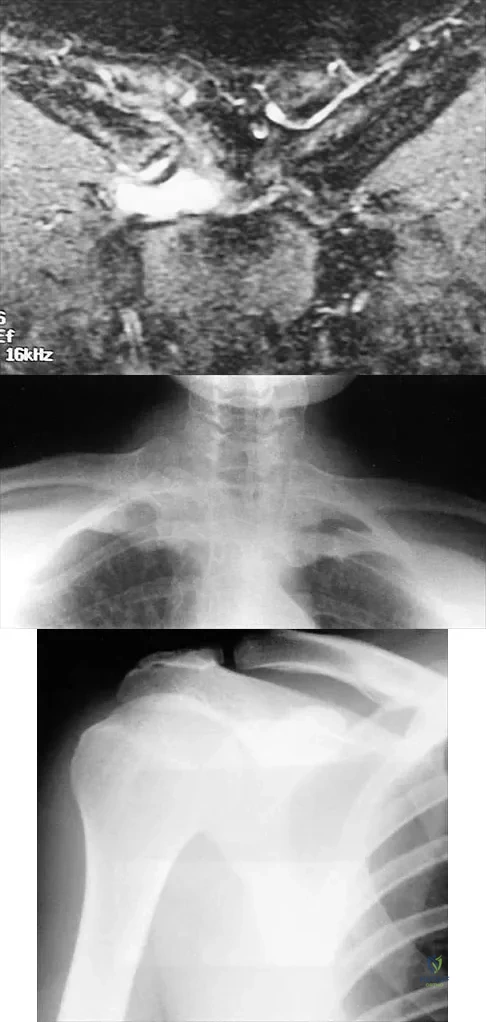

An axillary nerve lesion may cause weakness in the deltoid and the

The quadrilateral space in the shoulder contains which of the following structures?

A previously asymptomatic 40-year-old man injures his shoulder in a fall. Examination shows that he is unable to lift the hand away from his back while maximally internally rotated. An axial MRI scan of the shoulder is shown in Figure 14. What is the most likely diagnosis?

Figures 36a and 36b show the MRI scans of a patient who has shoulder weakness. What is the most likely diagnosis?

Figures 51a and 51b show subluxation of the

A 43-year-old former professional hockey player reports severe pain in his chest after being checked from the side in a pick-up hockey game. An MRI scan and plain radiographs are shown in Figures 25a through 25c. What is the most likely diagnosis?